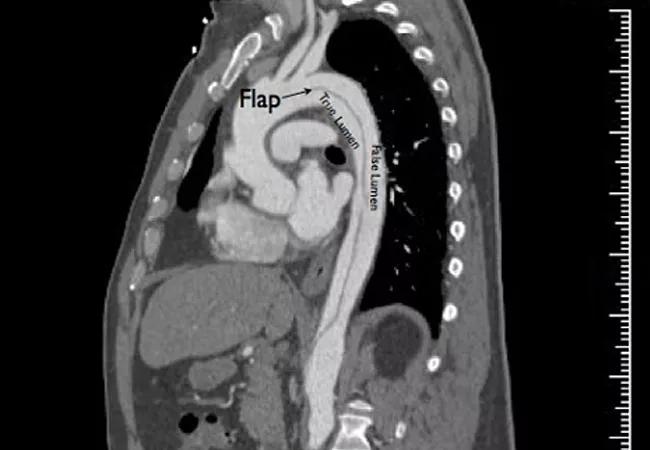

His blood pressure was 248/119 mmHg. CT revealed a descending thoracic aortic dissection (Figure 1). He had acute renal failure with an elevated creatinine that peaked at 2.4 mg/dL. His hypertension was eventually controlled on a five-drug regimen (clonidine, losartan, carvedilol, hydralazine and amlodipine). Despite this, his systolic pressure remained persistently above 160 mmHg and he had persistent back pain. His renal function stabilized at a creatinine of 1.8 mg/dL, indicating that he had lost almost half of his baseline kidney function.

On arrival here, his systolic blood pressure remained above 160 mmHg and he continued to report back pain. Review of his prior CT (Figure 1) revealed compression of most of his true lumen, compromising flow into the kidneys, which were perfused by the false lumen. He also had diminished lumen flow into his abdominal viscera (stomach, liver, intestines) and legs, although he remained asymptomatic in these vascular beds.

Figure 1. The patient’s CT at presentation.